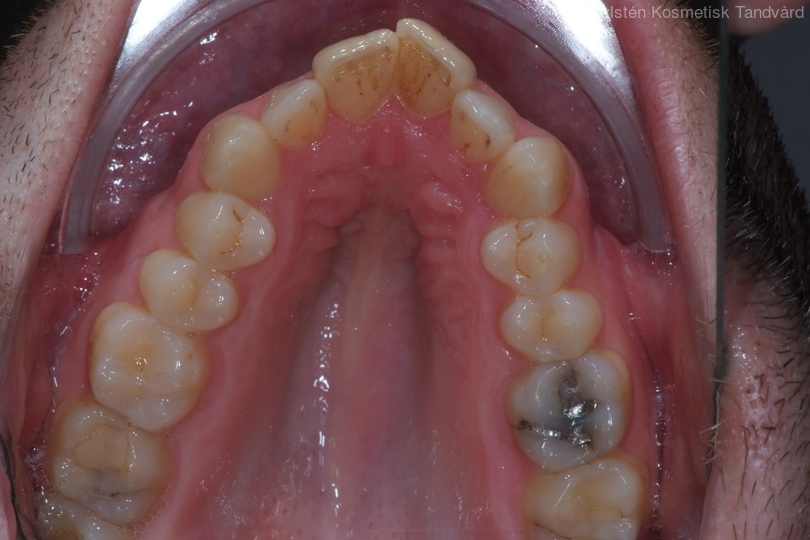

35-årig man med smal och trångställd tandbåge. Vill ha ett jämnt leende. Behandling bestod av knappt 9 månader med genomskinliga Invisalignskenor.